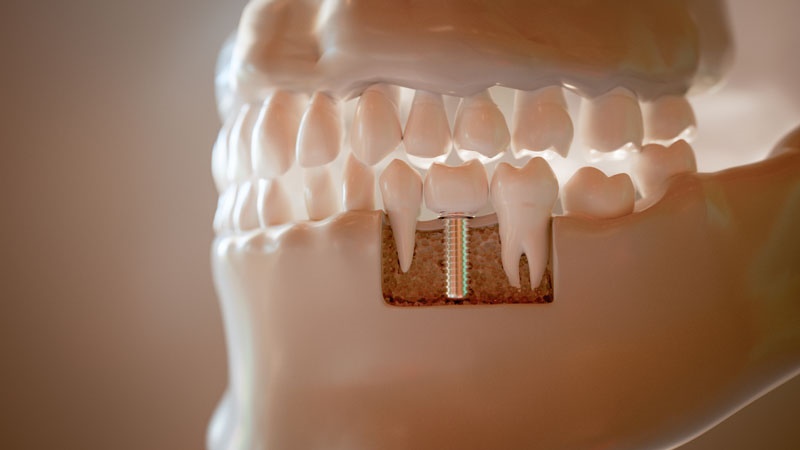

ایمپلنت دندان چیست و چگونه کار میکند؟

ایمپلنت دندان در واقع یک پیچ کوچک از جنس تیتانیوم است که در استخوان فک جایگذاری میشود و نقش ریشه دندان را ایفا میکند. روی این پایه، قطعهای به نام اباتمنت قرار میگیرد که تاج دندان را نگه میدارد. تاج دندان، بخش قابل مشاهده است و همانند دندان طبیعی ظاهر میشود.

با کاشت ایمپلنت، نیروی جویدن به استخوان فک منتقل میشود و از تحلیل استخوان جلوگیری میکند. برخلاف دندان مصنوعی متحرک یا پل ثابت، ایمپلنت نیاز به تراشیدن دندانهای مجاور ندارد و به طور مستقل عملکرد خود را انجام میدهد.